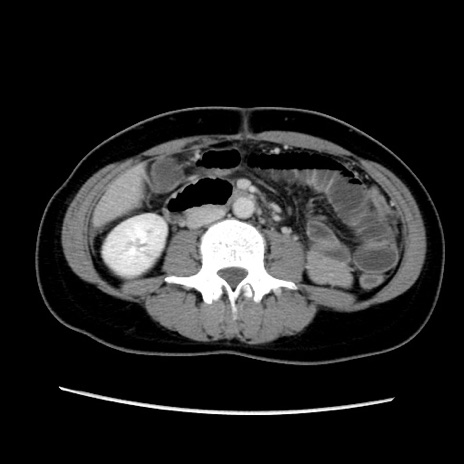

症例39(横断像)

【症例】40歳代女性

【主訴】上下腹部痛

【現病歴】2日目から下腹部痛あり。夜間は痛みで眠れなかった。昨日より上腹部痛と下痢が出現。臥位で痛みは軽快したため、休んでいた。本日になって臥位でも立位でも痛みが強くなってきたため救急要請。

【既往歴】子宮内膜症

【身体所見】部:平坦・軟、左上下腹部に圧痛あり、反跳痛あり。

【データ】WBC 21800、CRP 26.78